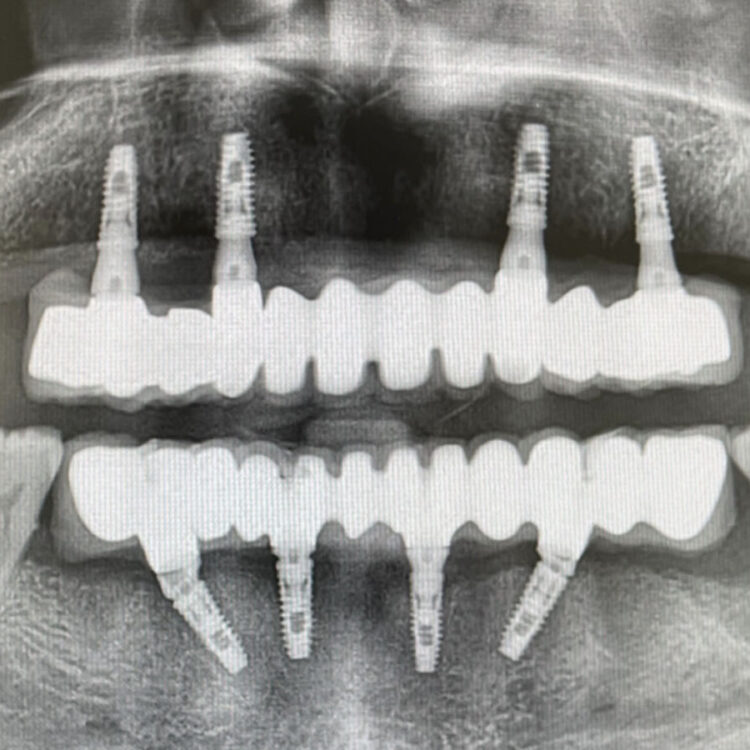

We can restore your smile, as well as speaking & eating ability with advanced prosthetics.A dental implant is a titanium screw that is inserted into the jawbone in place of a lost tooth or teeth, this merges with the bony tissue to serve as a natural tooth root.